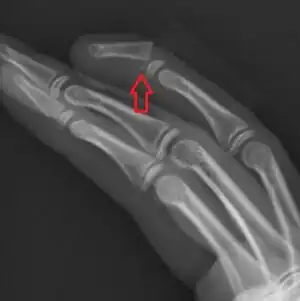

| Seymour fracture of the 4th finger distal phalanx | |

A Seymour fracture is a type of distal phalanx fracture and mallet finger that may occur in children.[1] It is associated with a nail bed injury.[1] Complications may include the stopping of finger type growth and deformity of the nail.[2]

It is a type of fracture through the growth plate, specifically a Salter-Harris type I or II pattern.[1]